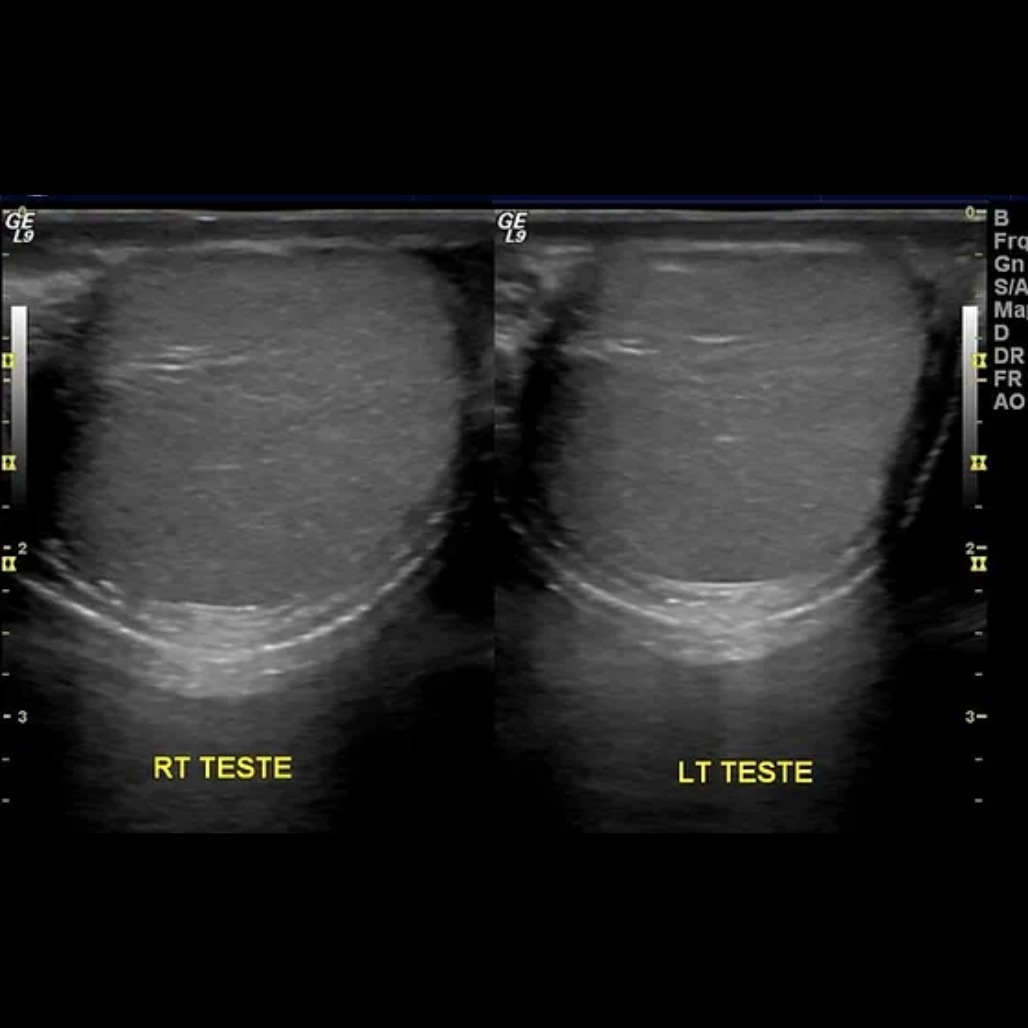

אולטרסאונד אשכים

בחינת מבנה האשך וגודלו, זרימת הדם בוורידים סביבו. בדיקה זו מבוצעת במקרים של זיהוי גוש באזור האשכים, הופעת כאבים או לשם אבחון בעיות פוריות בגברים.